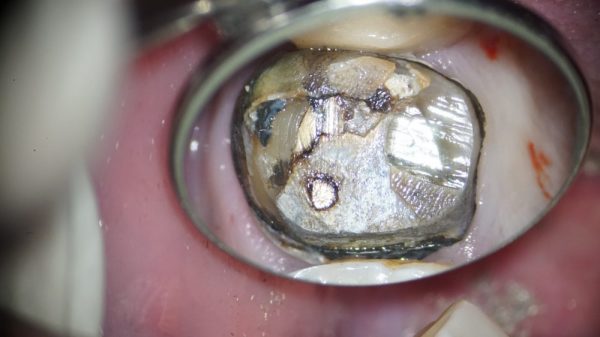

中が黒くなっています。これはまだ土台が入っていますので外していきます。

根の内部が見えてきました。

根の内部が見えてきました。

ここで真ん中の根の内部を触らずにまずは外側の虫歯をしっかり除去することが大事です。

しっかり虫歯を除去できました。

しっかり虫歯を除去できました。